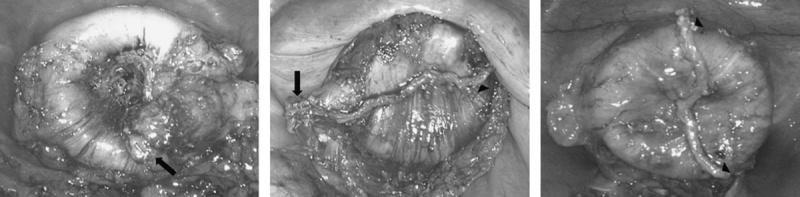

Laparoscopic intracorporeal colorectal anastomosis with double stapling technique is difficult because of unsuitable cutting angle in narrow pelvic cavity. For reasons of tilted and long linear staple line of rectal stump, circular anastomotic plane can make multiple intersections. The present study was designed to assess whether multiple intersections after double stapling technique is the risk factor of anastomotic complication in laparoscopic colorectal surgery.

In total, 128 consecutive left colon and rectal cancer patients who underwent laparoscopic rectal resection with double stapling technique were enrolled in this study. In all cases, operator tried to reduce intersections by inversion and invagination techniques. They were subdivided into 3 groups: 58 patients with no intersection of staple lines (group A), 62 patients with 1 point of intersection (group B) and 8 patients with 2 points of intersection (group C). Intraoperative air leakage, incomplete cut ring, postoperative bleeding, anastomotic stenosis, and leakage were compared between the 3 groups.

The number of intersections of staple lines is associated with anastomotic leakage, and the inversion technique is a useful method for avoiding anastomotic leakage. Using an appropriate technique by skilled operator, double stapling technique for laparoscopic anterior resection is safe and feasible.